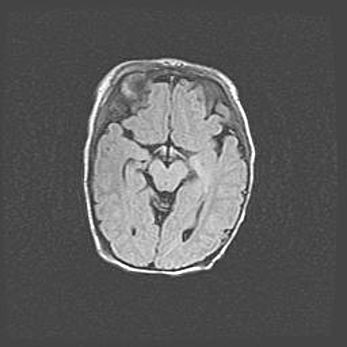

Лейкомаляция с кистозно-глиозной дегенерацией головного мозга.

Возраст: 2 месяца 25 дней

Вес: 6400 г

Окружность головы: 40 см

Срок гестации: 41 неделя

Лейкомаляцию относят к ишемически-гипоксическим повреждениям головного мозга, диагностируемым у новорожденных. При лейкомаляции в головном мозге обнаруживают очаги некроза, возникшие после тяжелой гипоксии и нарушения кровотока. В процессе морфогенеза очаги проходят три стадии: 1) развития некроза, 2) резорбции и 3) формирования глиозного рубца или кисты. Перивентрикулярная лейкомаляция (ПЛ) встречается примерно в 12% случаев среди новорожденных, обычно – у недоношенных детей, причем, частота ее зависит от массы, с которой младенец появился на свет. Наибольшее число малышей страдает лейкомаляцией, если масса при рождении 1500-2500 г.